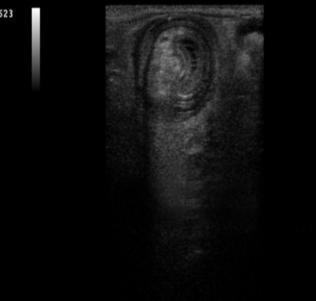

急性肠套叠是婴儿期的一种特有疾病,一岁以内多见,占60%~65%,其中又以4~10个月婴儿多见。2岁以后随年龄增长发病率逐年减少,5岁罕见。这是由于婴幼儿回盲部肠系膜尚未完全固定、活动度较大,因此容易出现肠套叠。根据调查显示,肠套叠的男婴发病率较高,男女孩的发病率之比约为2:1~3:1。肠套叠一年四季均有发病,以春季发病率较高,可能与上呼吸道感染及胃肠道病毒感染有关,夏冬次之,秋季较少见。临床排除肠套叠时,B超是首选。在B超下,肠套叠的部位可显示出边界清楚的包块。在肠管的横断面上呈现大环套小环的特征,即“同心圆征”。如下图所示。其表现为:外圆为均匀的低回声环带(系鞘部的肠壁回声),外圆内又有一个小低回声环带,形成内圆。内外圆之间为高回声环。形成“同心圆”。这可不是小虎队“爱”的魔力转圈圈后形成的哦。

肠套叠的同心圆症